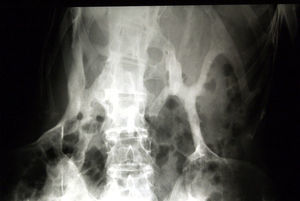

Los recién nacidos con FOP tienen un aspecto normal excepto por la presencia (en la práctica totalidad de ellos) de malformaciones en el dedo gordo del pie, siendo el hallux valgus congénito el sello más característico de la enfermedad (fig. 1)13,14. Aunque se suelen reconocer más tarde (e incluso pasan inadvertidas o son erróneamente interpretadas), el componente displásico de la FOP se puede manifestar por diversas anomalías esqueléticas congénitas que aparecen con una frecuencia variable pero casi siempre elevada. Entre estas malformaciones destacan: otras anomalías en los dedos de las manos y los pies distintas de las del dedo gordo del pie (acortamiento de falanges, metatarsianos y metacarpianos, sinostosis, clinodactilia)15; aumento de tamaño y fusión de la facetas posteriores con hipoplasia del cuerpo vertebral en la columna cervical (fig. 2), que puede acabar formando un bloque16–18; osteocondromas, sobre todo evidentes en la región medial de la tibia19, y cuello femoral corto y ancho20.

En las fases iniciales, antes de la formación de placas de hueso heterotópico, los errores de diagnóstico son frecuentes, confundiéndose con procesos como la fibromatosis agresiva juvenil, el linfedema o el sarcoma de partes blandas12,32,33. Sin embargo, es muy importante tener en cuenta que, aunque los nódulos incipientes puedan prestarse a confusión, la presencia concomitante de la típica malformación congénita del dedo gordo del pie (fig. 1) permite realizar el diagnóstico de certeza. En todo caso, el test genético apropiado confirmaría la enfermedad, haciendo innecesarias otras pruebas y medidas terapéuticas que pueden ocasionar un daño irreversible34. A este respecto, hay que insistir en la inutilidad de la biopsia, la cual, al igual que los procedimientos quirúrgicos ortopédicos, deben evitarse, ya que de manera habitual conduce a un empeoramiento de la lesión33-35.